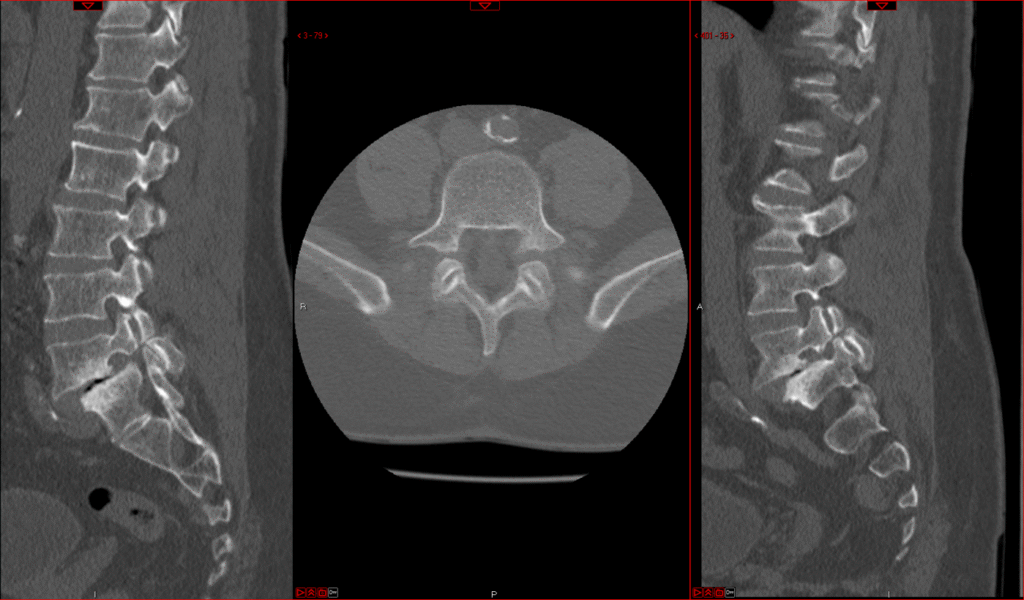

Transforaminal Lumbar Spine Fusion